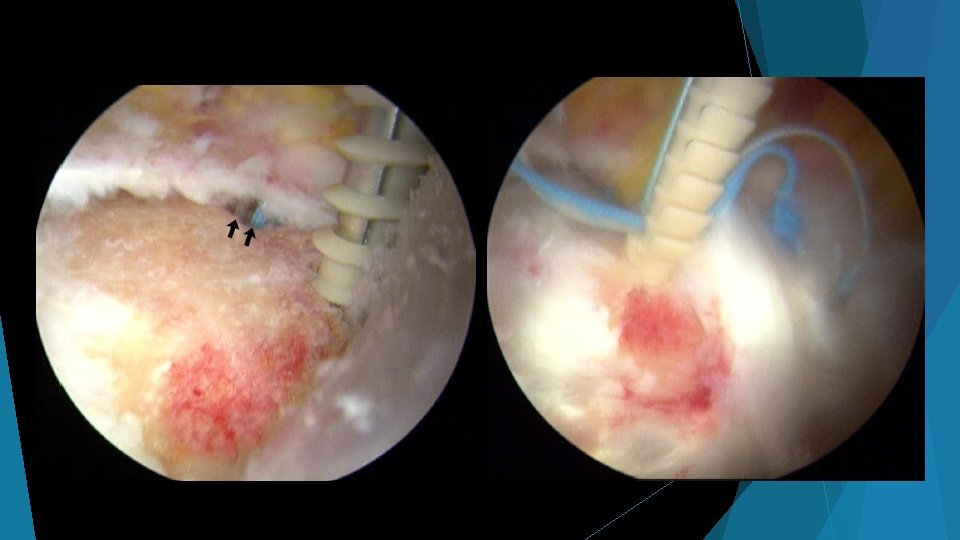

Abductor repair surgery